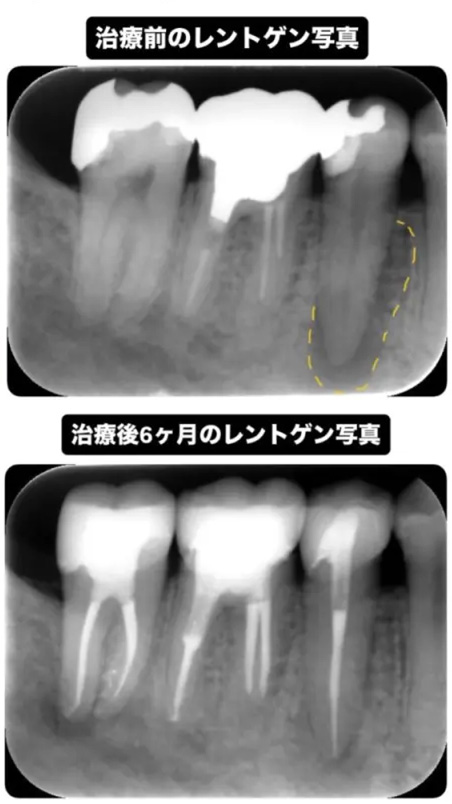

根管治療を行った後、骨が回復するまで6ヶ月ほど経過観察を行います。こちらは治療後6ヶ月のレントゲンとCTの写真です。

-

まだ少し黒い影はあるものの、薄く骨のようなものがモヤっとできており、溶けていた根っこの先の骨が大きく回復傾向にあるのがわかります。